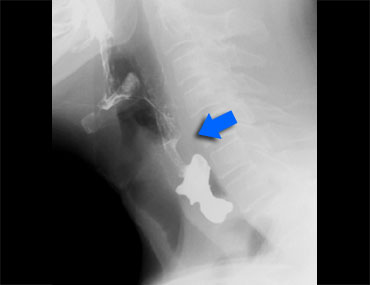

TRÁI: túi thừa nhỏ. GIỮA và PHẢI: túi thừa Zenker thực sự do đóng sớm của cơ nhẫn hầu (mũi tên vàng)

Túi thừa Zenker

Túi thừa Zenker luôn là hậu quả của rối loạn chức năng cơ nhẫn hầu.

Đóng sớm của cơ nhẫn hầu dẫn đến tăng áp lực trong hạ hầu, ngay phía trên cơ nhẫn hầu, khi sóng áp lực của các cơ khít hầu đẩy bolus xuống dưới.

Áp lực tăng này có thể gây phồng ra tại điểm yếu trên thành hầu sau (khe hở Killian).

Ban đầu sẽ tạo thành một túi nhỏ, theo thời gian có thể phát triển và hình thành túi thừa Zenker thực sự (Hình).